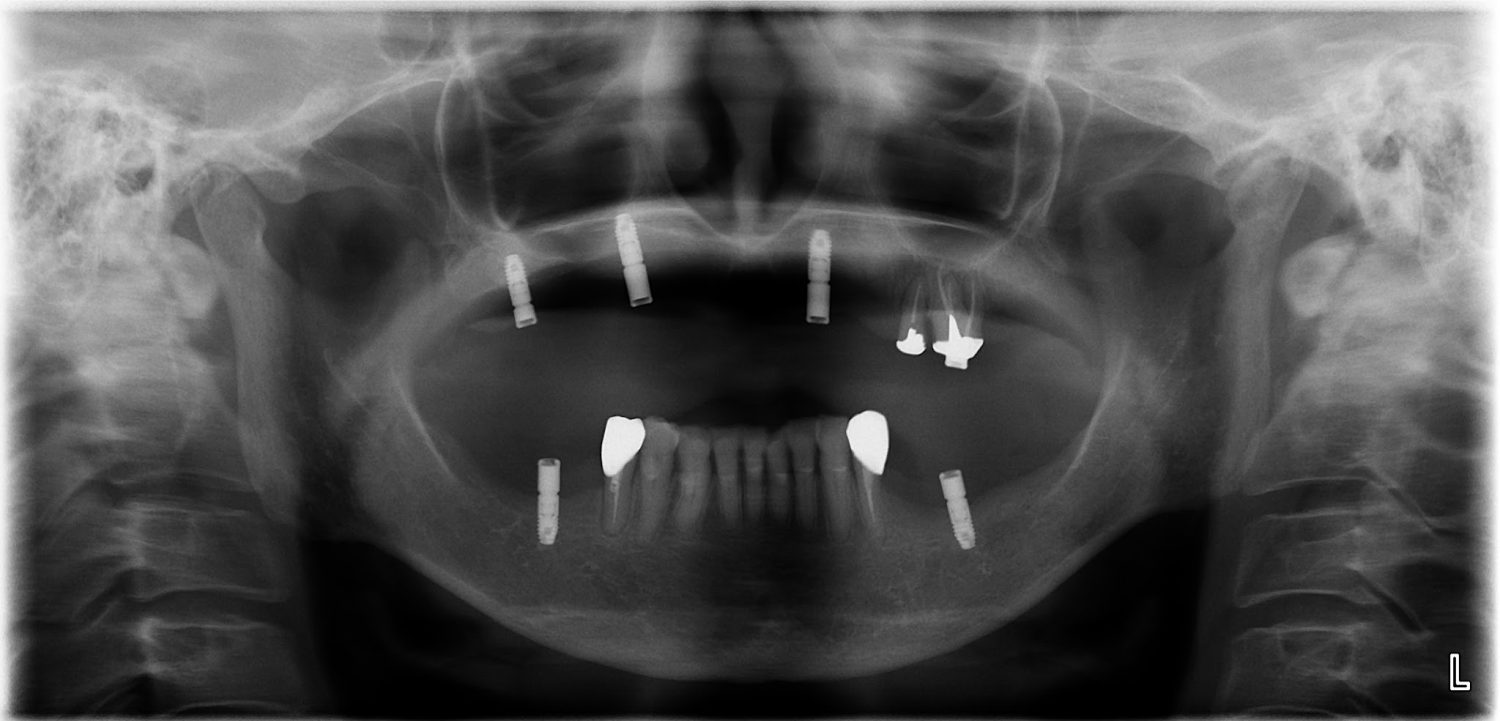

インプラント治療の症例紹介④

Before

After

主訴

義歯による疼痛

治療内容

下顎舌側に骨隆起があり義歯困難な状態。保存不可能な歯の抜歯を行い、インプラントを埋入し咬合再構成を行った。

治療費

2,851,200円(税込)

治療期間

29ヶ月

通院回数

26回

想定されたリスク

※咬合力の強い方なので、予防的にマウスピースの装着が必要。インプラント周囲炎の恐れがありました。

濱 仁隆先生

浜歯科

歯の欠損の対合歯の挺出等を修正し咬合平面を揃え咬合再構成を行った症例。